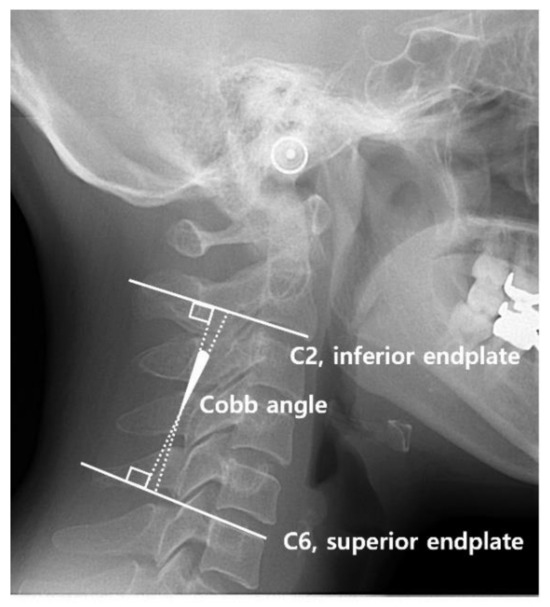

- C2–C6 Cobb method (Figure 3) [28]: The Cobb angle is the angle between the two perpendicular lines made from the inferior margin of C2 and the superior margin of C6. The angle is considered to be positive when the superior margin of C6 was more clockwise than the inferior margin of C2. The cervical spine types are classified according to the following criteria: If the Cobb angle is >7° but <20°, it is a ‘lordotic’ curvature type; if it is >−7° but <7°, it is a ‘straight’ curvature type; and if it is −7° or less, it is a ‘kyphotic’ curvature type.